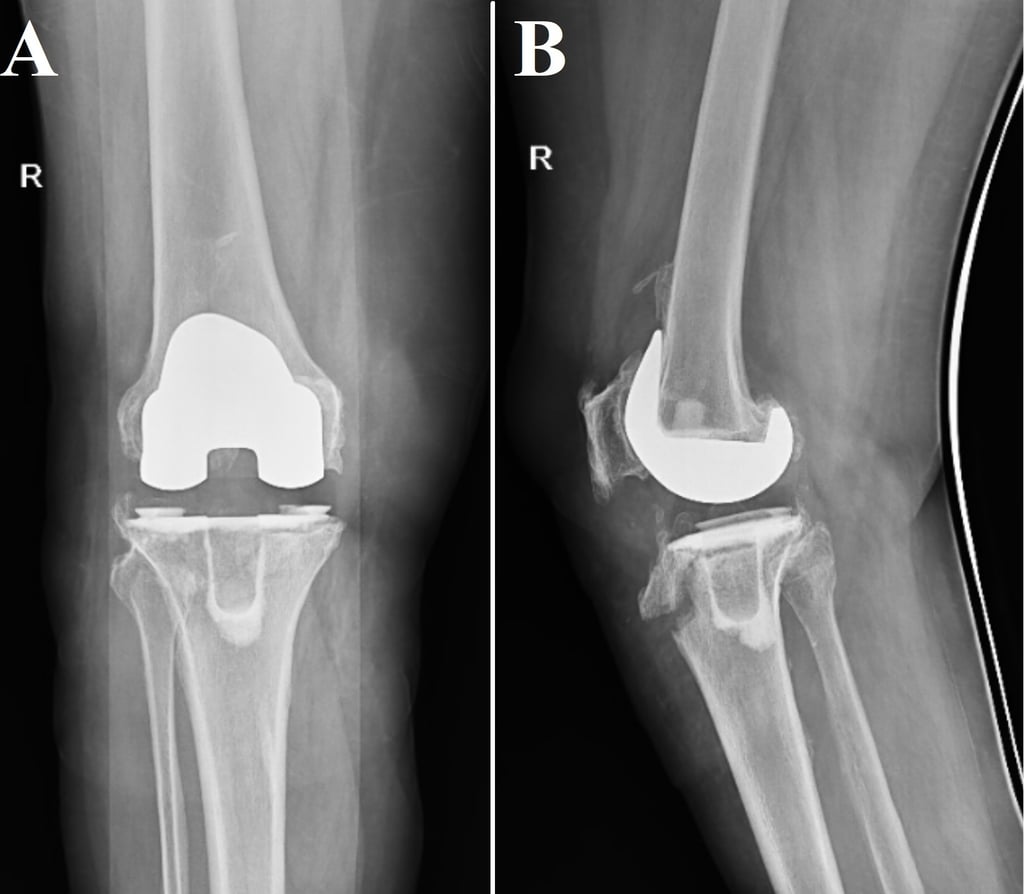

Total knee arthroplasty with long tibial stem for tibial stress fractures with knee osteoarthritis: Two birds with one stone

The treatment and outcome of tibial stress fractures concomitant with knee osteoarthritis (OA) are complicated. The aim of this study was to evaluate the functional and radiological outcome of total knee arthroplasty with long tibial stem as a treatment for patients having knee OA and tibial stress fracture.